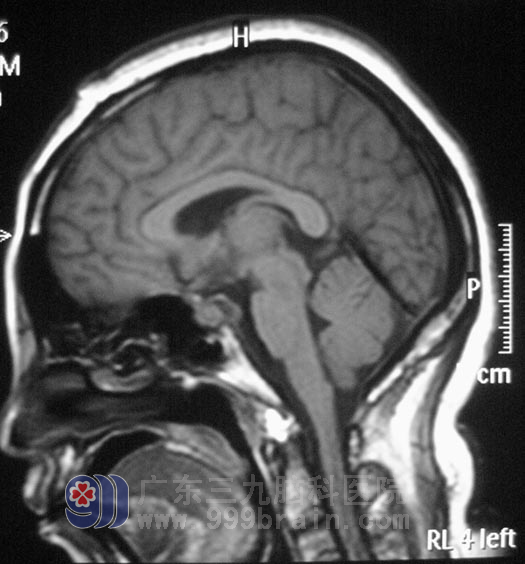

神经外五科鲁明主任分析后指出:许女士右眼视力下降与右侧鞍区占位有关,从头颅MRI上看,右侧鞍区占位内有许多血管通过,右侧颈内动脉被肿瘤包裹,有受压变细,术中分离肿瘤可能损伤颈内动脉。经过慎重考虑决定先行造影栓塞后再行手术治疗,避免术中大量出血,减少手术的风险性。3月20日,许女士在介入室行肿瘤部分供血血管栓塞术。3月22日,由鲁明主任主刀,在全麻下行“右侧蝶骨嵴脑膜瘤切除术”, 术中见肿瘤位于右侧中颅窝底,其基底部位于右侧蝶骨嵴、前床突位置,包绕右侧颈内动脉并延伸至对侧鞍旁,右侧视神经被肿瘤包绕并向上抬起,右侧动眼神经、外展神经被肿瘤压迫位于肿瘤外侧,肿瘤质地较软,血供丰富。显微镜下小心分离,将肿瘤分块全切,椎动脉及其分支位于肿瘤后下方,过程中右侧颈内动脉及其分支、椎动脉及其分支、双侧视神经、外展神经及动眼神经保护完好,手术成功完成。术后患者病理结果为:(右侧蝶骨嵴)脑膜皮细胞型脑膜瘤,WHOI级。

▲手术后影像